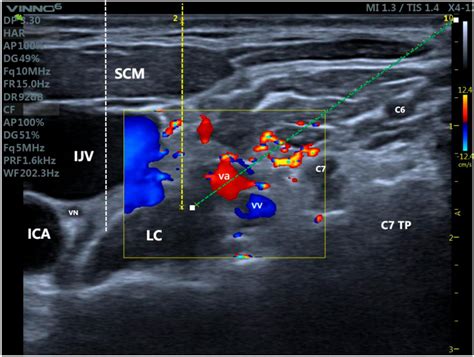

The stellate ganglion is a critical component of the sympathetic nervous system, which plays a crucial role in regulating various bodily functions such as heart rate, blood pressure, and sweating. Located in the neck, it is formed by the fusion of the inferior cervical and first thoracic ganglia. The stellate ganglion is a key player in the body’s “fight or flight” response, making it a target for interventions aimed at managing conditions related to stress and pain.

The Stellate Ganglion Block procedure is typically performed under fluoroscopic guidance to ensure precise placement of the anesthetic. Here is a step-by-step overview of what patients can expect:

1. The patient is positioned lying down on their back with their head slightly turned to the side.

2. The skin over the injection site is cleaned and numbed with a local anesthetic.

3. Using fluoroscopy, the physician guides a needle to the stellate ganglion.

4. A small amount of contrast dye is injected to confirm the correct position of the needle.

5. The anesthetic is then injected into the stellate ganglion.

6. The patient is monitored for a short period to ensure there are no immediate complications.